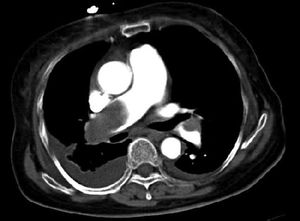

Diagnosis??

Empyema right lung? Pulmonary emboli ?

Perfectly emboli, u r awesome

Thanks, did the patient have pleural effusion of right and left lung, too?

Embolism